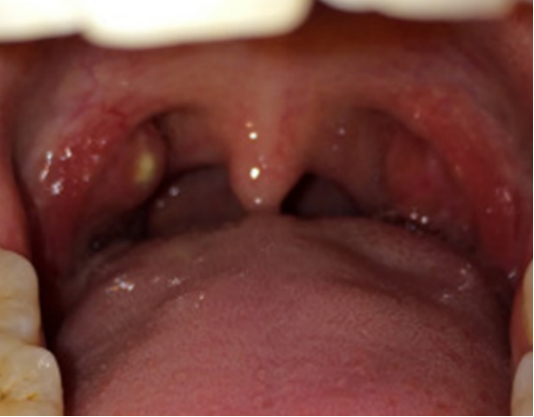

小儿扁桃体表面可见黄白色脓包,或在隐窝口处有黄白色、灰白色豆渣样渗出物,可连成一片形似假膜,一般有咽痛、发热、流涎、拒食等相关表现。

患者咽痛逐渐加重,吞咽困难,唾液外流,体温可达39℃以上。扁桃体周围隆起白色脓包,腭弓及软腭红肿突出,腭垂(悬雍垂)水肿。

可见咽侧壁、后壁黏膜严重弥漫性肿胀充血,有白色脓点或较大的白色脓包,腭垂、腭弓水肿。小儿咽痛剧烈,吞咽困难,有大量黏稠唾液,伴脓血性分泌物。